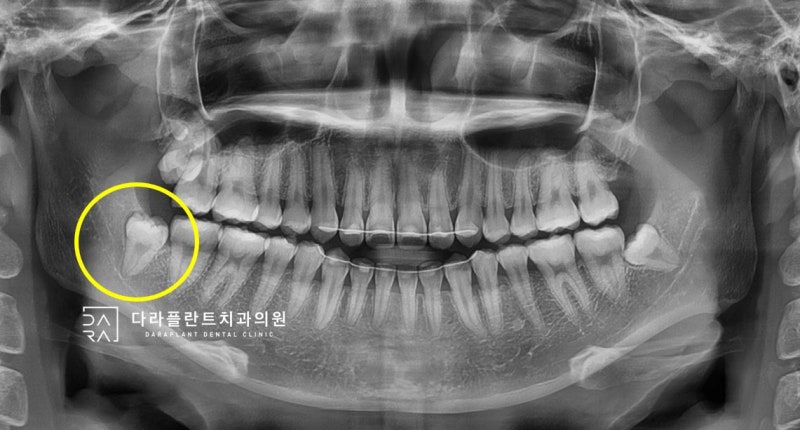

오늘은 매복 사랑니 발치 케이스를 살펴보도록 하겠습니다. 20대 여성 환자로 사랑니 부분이 불편하여 저희 병원에 내원하였습니다. 파노라마 X선 먼저 보도록 하겠습니다.

양쪽에 상하 1개씩 총 4개의 사랑니가 있습니다. 그 중 왼쪽 아래가 불편하기 때문에 왼쪽 상하를 먼저 발치하도록 하겠습니다. 파노라마 위에서 왼쪽 상하는

여기 있습니다. 이 중에서

이처럼 노란 색에 동그란 이가 부모 모릅니다. 위의 부모 모르를 카미다 케동이란 공기 주머니와 뿌리가 근처에 있네요위의 부모 모르를 발치할 때 처음 고려하는 것은 얼마나 깊은 매복되어 있습니까. 그리고 환자의 입이 얼마나 잘 열지도 중요합니다. 입의 열림 상태를 “개구량”이라고 합니다.위의 부모 모르면 생각보다 잘 보이지 않습니다. 해도, 입이 열리지 않으면 더 잘 보이지 않고.만약 입이 안 떨어지게 숨은 정도가 심한 경우는 위의 부모 모른다고 해도 난이도가 높아지는 일이 있습니다. 다행히, 이 환자의 위 매복 부모 모르는 경우 난이도가 그렇게 높은 보이지 않습니다. 치아 뿌리도 열지 않기 때문에 몇초에서 날 정도의 난이도요.그 다음, 아래의 부모 모른다.아래의 부모 모르는 경우 가장 중요하게 생각하는 것은 매복 부모 모른다고 신경관까지 거리입니다. 하악 신경과 거리가 가까울수록 발치 난이도는 커졌고 발치 후 합병증도 생길 가능성이 높습니다. 덕양구 부모 모르는 발치과 다라 플랜트로 치과용 CT를 촬영하고 매복 부모 모른다고 신경의 3차원적 위치를 확인합니다.